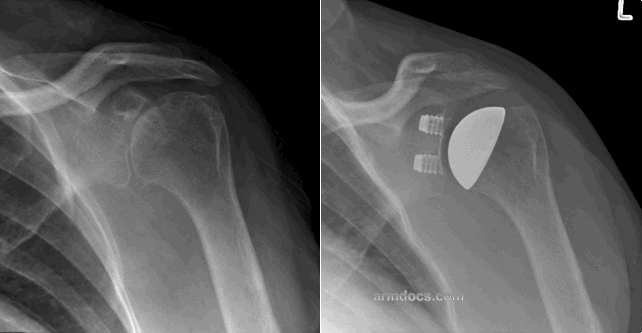

Humeral head resurfacing: In this procedure the head of the humerus (the ball of the joint) is resurfaced with a metal “cap”. This provides a smooth and hard bearing surface on the ball side of the joint and may be appropriate where only one side of the joint is damaged in conditions such as avascular necrosis of the humeral head. It generally provides very good pain relief if the natural socket of the shoulder is relatively healthy. The procedure conserves bone making subsequent revision surgery less challenging.

Total shoulder resurfacing: Both the ball and the socket of the joint are resurfaced in this procedure. This is a technically demanding operation and is indicated for conditions where both surfaces of the joint are damaged such as in osteoarthritis or rheumatoid arthritis. A functionally intact rotator cuff is a prerequisite. The procedure provides excellent pain relief and improvement in function. The procedure conserves bone making subsequent revision surgery less challenging.